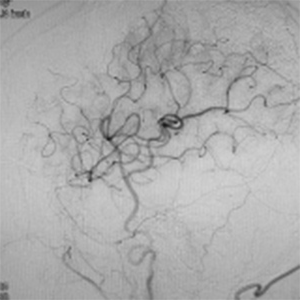

程度が軽い場合には、薬の治療(内科治療)のみを行います。程度が軽い方は、お薬だけで脳梗塞の再発を防げる場合も多いです。しかし、程度がひどい場合、脳血流が低下している場合には、お薬だけでは、2年で20%前後の人が脳梗塞の再発を起こすともいわれております。狭窄や閉塞は慢性的に詰まっており、再開通させることはできません。そのかわりに、頭皮の血管(主に、浅側頭動脈)を剥離し、頭の中の脳血管に顕微鏡を用い吻合することにより、脳の血流量を外から増やすバイパス手術を行います。浅側頭動脈中大脳動脈バイパス術(STAMCAバイパス術)といいます。バイパス術で脳の血流を増やすことにより、脳梗塞の再発する危険性を大きく減らすことできます。現在のガイドラインで推奨されている手術適応は、簡単にいうと73歳以下の比較的元気な方で、脳の血流が著しく低下している方です。最近は、平均寿命も延び、高齢な元気な方も増えております。国内、海外でも高齢者に対するバイパス手術で良好な成績を示す報告は増えております。当院でも、全身状態やほかのご病気の有無を確認し、全身状態が良い場合には、高齢者でも、十分な術前検査を行ったうえで、バイパス手術を行っており、良好な成績を出しております。

バイパス術により脳血流が正常化